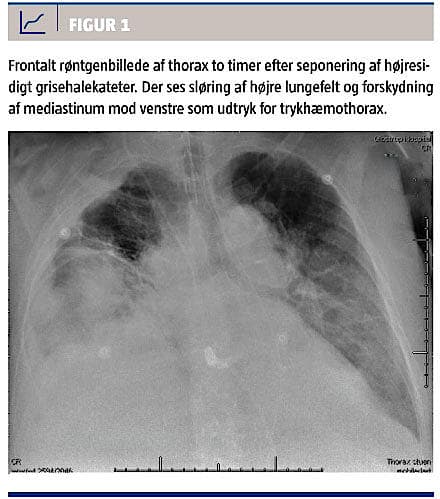

Da patienten ankom til vores afdeling, var der atter betydende pleuraeffusion, og der var indikation for fornyet anlæggelse af PTK. Koagulationsstatus

før anlæggelsen var normal (trombocytniveau 281 × 109/l, international normaliseret ratio: 1,0), og patienten fik heller ikke trombocythæmmere. Der blev UL-vejledt anlagt et 7 Ch PTK af den vagthavende radiolog, og kateteret var umiddelbart velfungerende med udtømning af strågul væske. Dagen efter seponeredes PTK uden anmærkninger. Omkring en time efter seponeringen blev patienten pludselig hæmodynamisk og respiratorisk ustabil og klagede over smerter i den side af thorax, hvorfra PTK var blevet seponeret. Ved stetoskopi blev der på samme side fundet nedsat respirationslyd. Røntgenoptagelse af thorax viste ingen pneumothorax, men der var en større mængder nytilkommen væske i thoraxhulen, og der var mistanke om hæmothorax. Der blev påbegyndt behandling med blodkomponenter og tranexamsyre. Trods dette blev patienten tiltagende hæmodynamisk og respiratorisk ustabil med tiltagende laktatacidose. En fornyet røntgenoptagelse af thorax efter yderligere en time (Figur 1) viste tiltagende sløring på højre side og nu med mediastinal overskydning som udtryk for trykhæmothorax. På vital indikation blev der anlagt et højresidigt pleuradræn 24 Ch. Ved anlæggelsen var der tydeligt overtryk i pleurahulen, og drænet fungerede umiddelbart med udløb af stærk blodig væske. Patientens hæmodynamiske tilstand rettede sig, og hun blev akut overflyttet til et andet sygehus mhp. thoraxkirurgisk intervention. Efter tre ugers yderligere intensivophold blev hun overført til et rehabiliteringscenter og blev siden udskrevet til eget hjem.